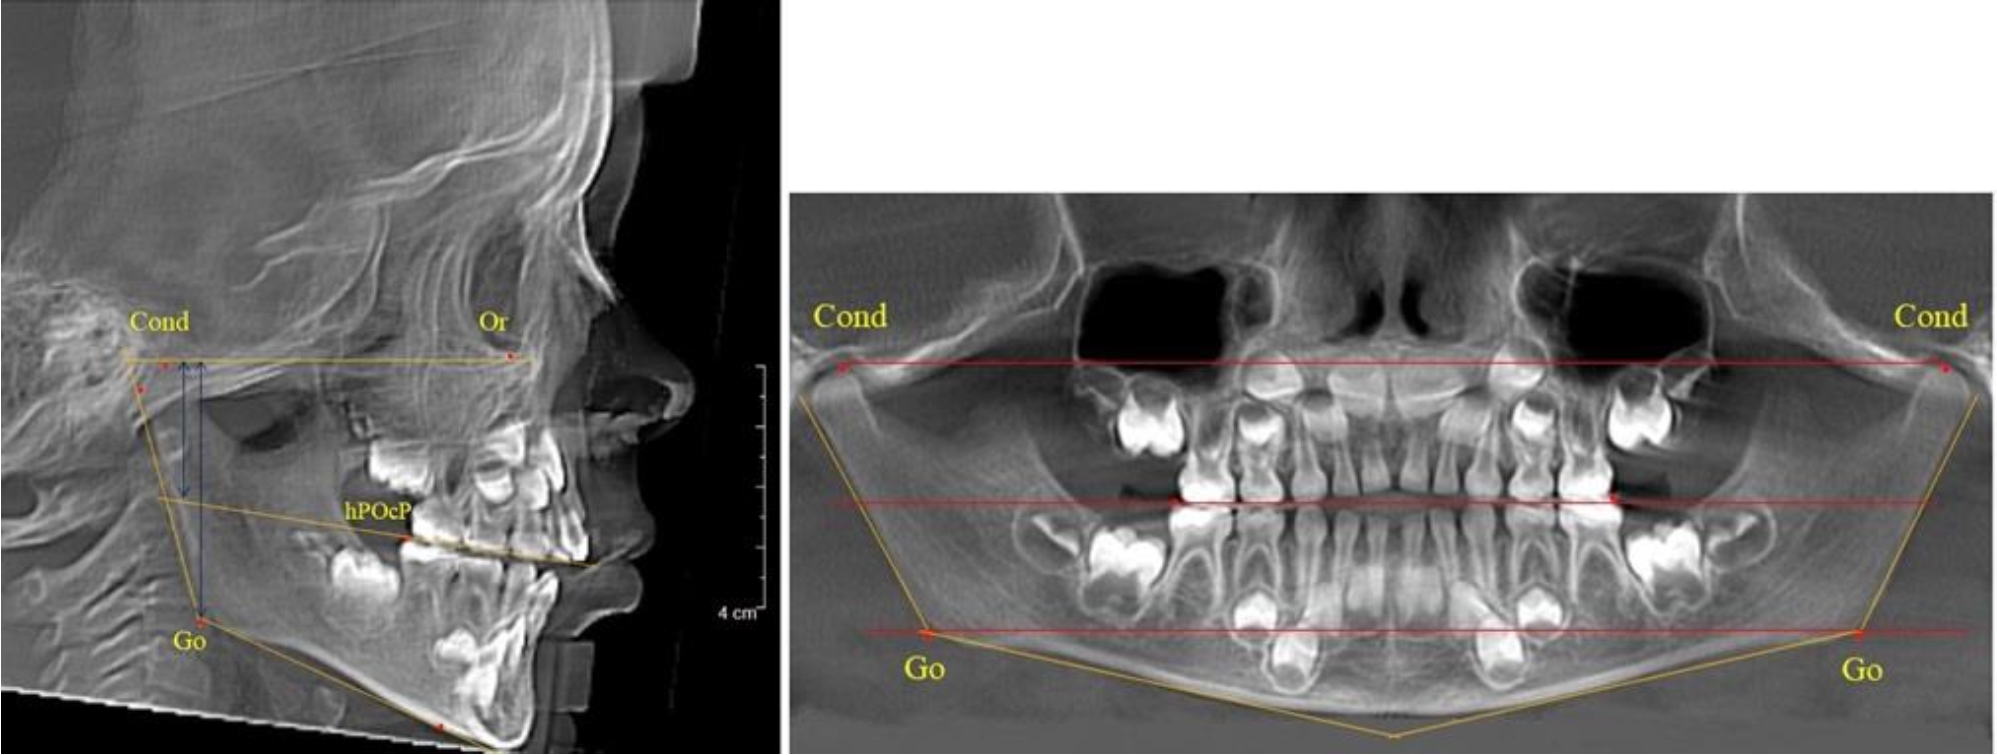

В 3-й группе были проанализированы 9 телерентгенограмм и 9 ортопантомограмм, что составило (8,49 ± 2,71) % от числа изученных рентгенограмм (рис. 3).

Рис. 3. ТРГ и ОПТГ пациента после смены молочных резцов

На всех рентгенограммах произошла смена молочных резцов постоянными. Окклюзионная линия делила ветвь на два отдела.

Высота ветви у детей у детей 3-й группы составляла (51,07 ± 2,72) мм, что было достоверно больше, чем у детей 1-й группы (р ˂ 0,05). При этом высота верхней окклюзионно-суставной части была (29,06 ± 1,44) мм, а нижней – (22,01 ± 1,59) мм. Высота верхней части была больше нижней, что и определяло особенности соразмерности частей ветви нижней челюсти в анализируемый возрастной период.

Относительные показатели соразмерности частей ветви нижней челюсти показали, что отношение высоты верхней части ветви к нижней в среднем составляло 1,32 ± 0,14. Отношение общей высоты ветви к верхней ее части составляло 1,75 ± 0,12, а отношение общей высоты ветви к нижней ее части было 2,32 ± 0,17, что и определяло особенности соразмерности частей ветви нижней челюсти в анализируемый возрастной период.